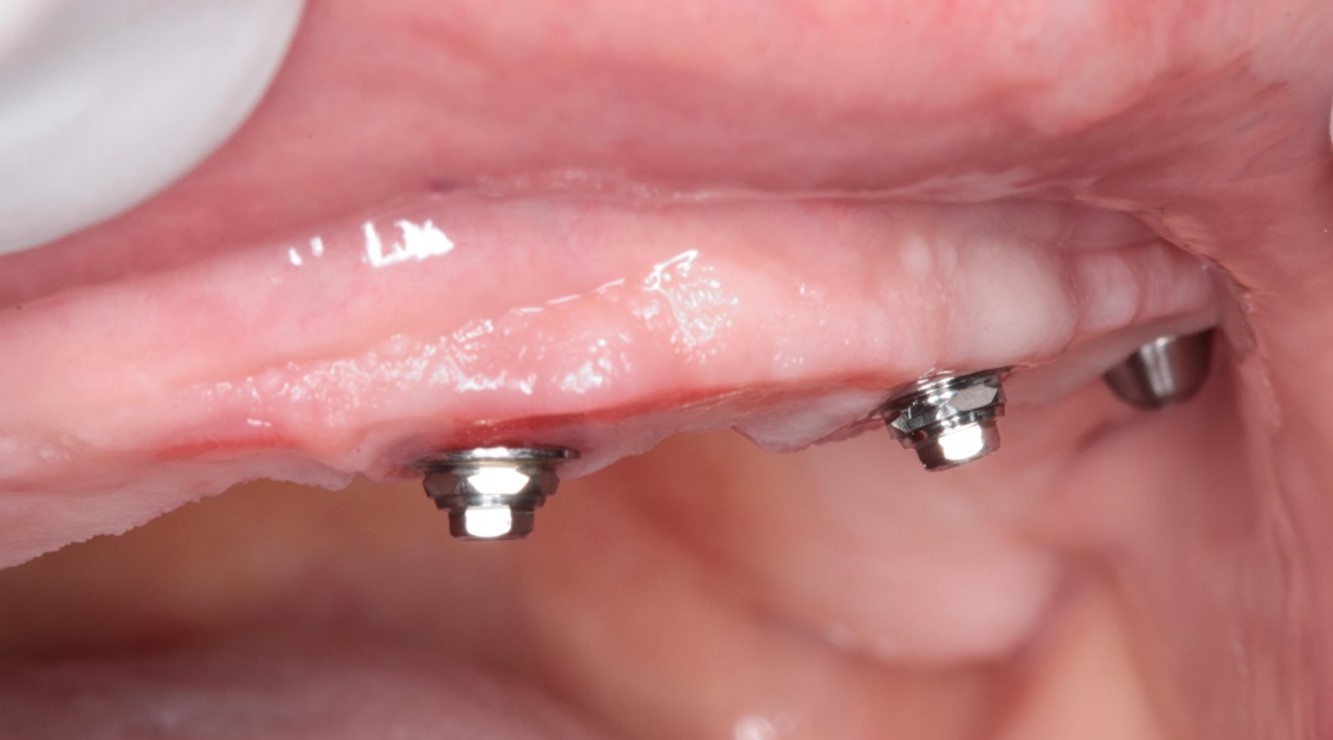

FIG. 08 – Instalação dos mini pilares angulados de 30 graus nos posteriores e retos nos anteriores.

FIG. 11 – Aspecto do tecido mole após 17 meses da cirurgia.

FIG. 13a b c – Aspecto dos tecidos moles após 26 meses da cirurgia.